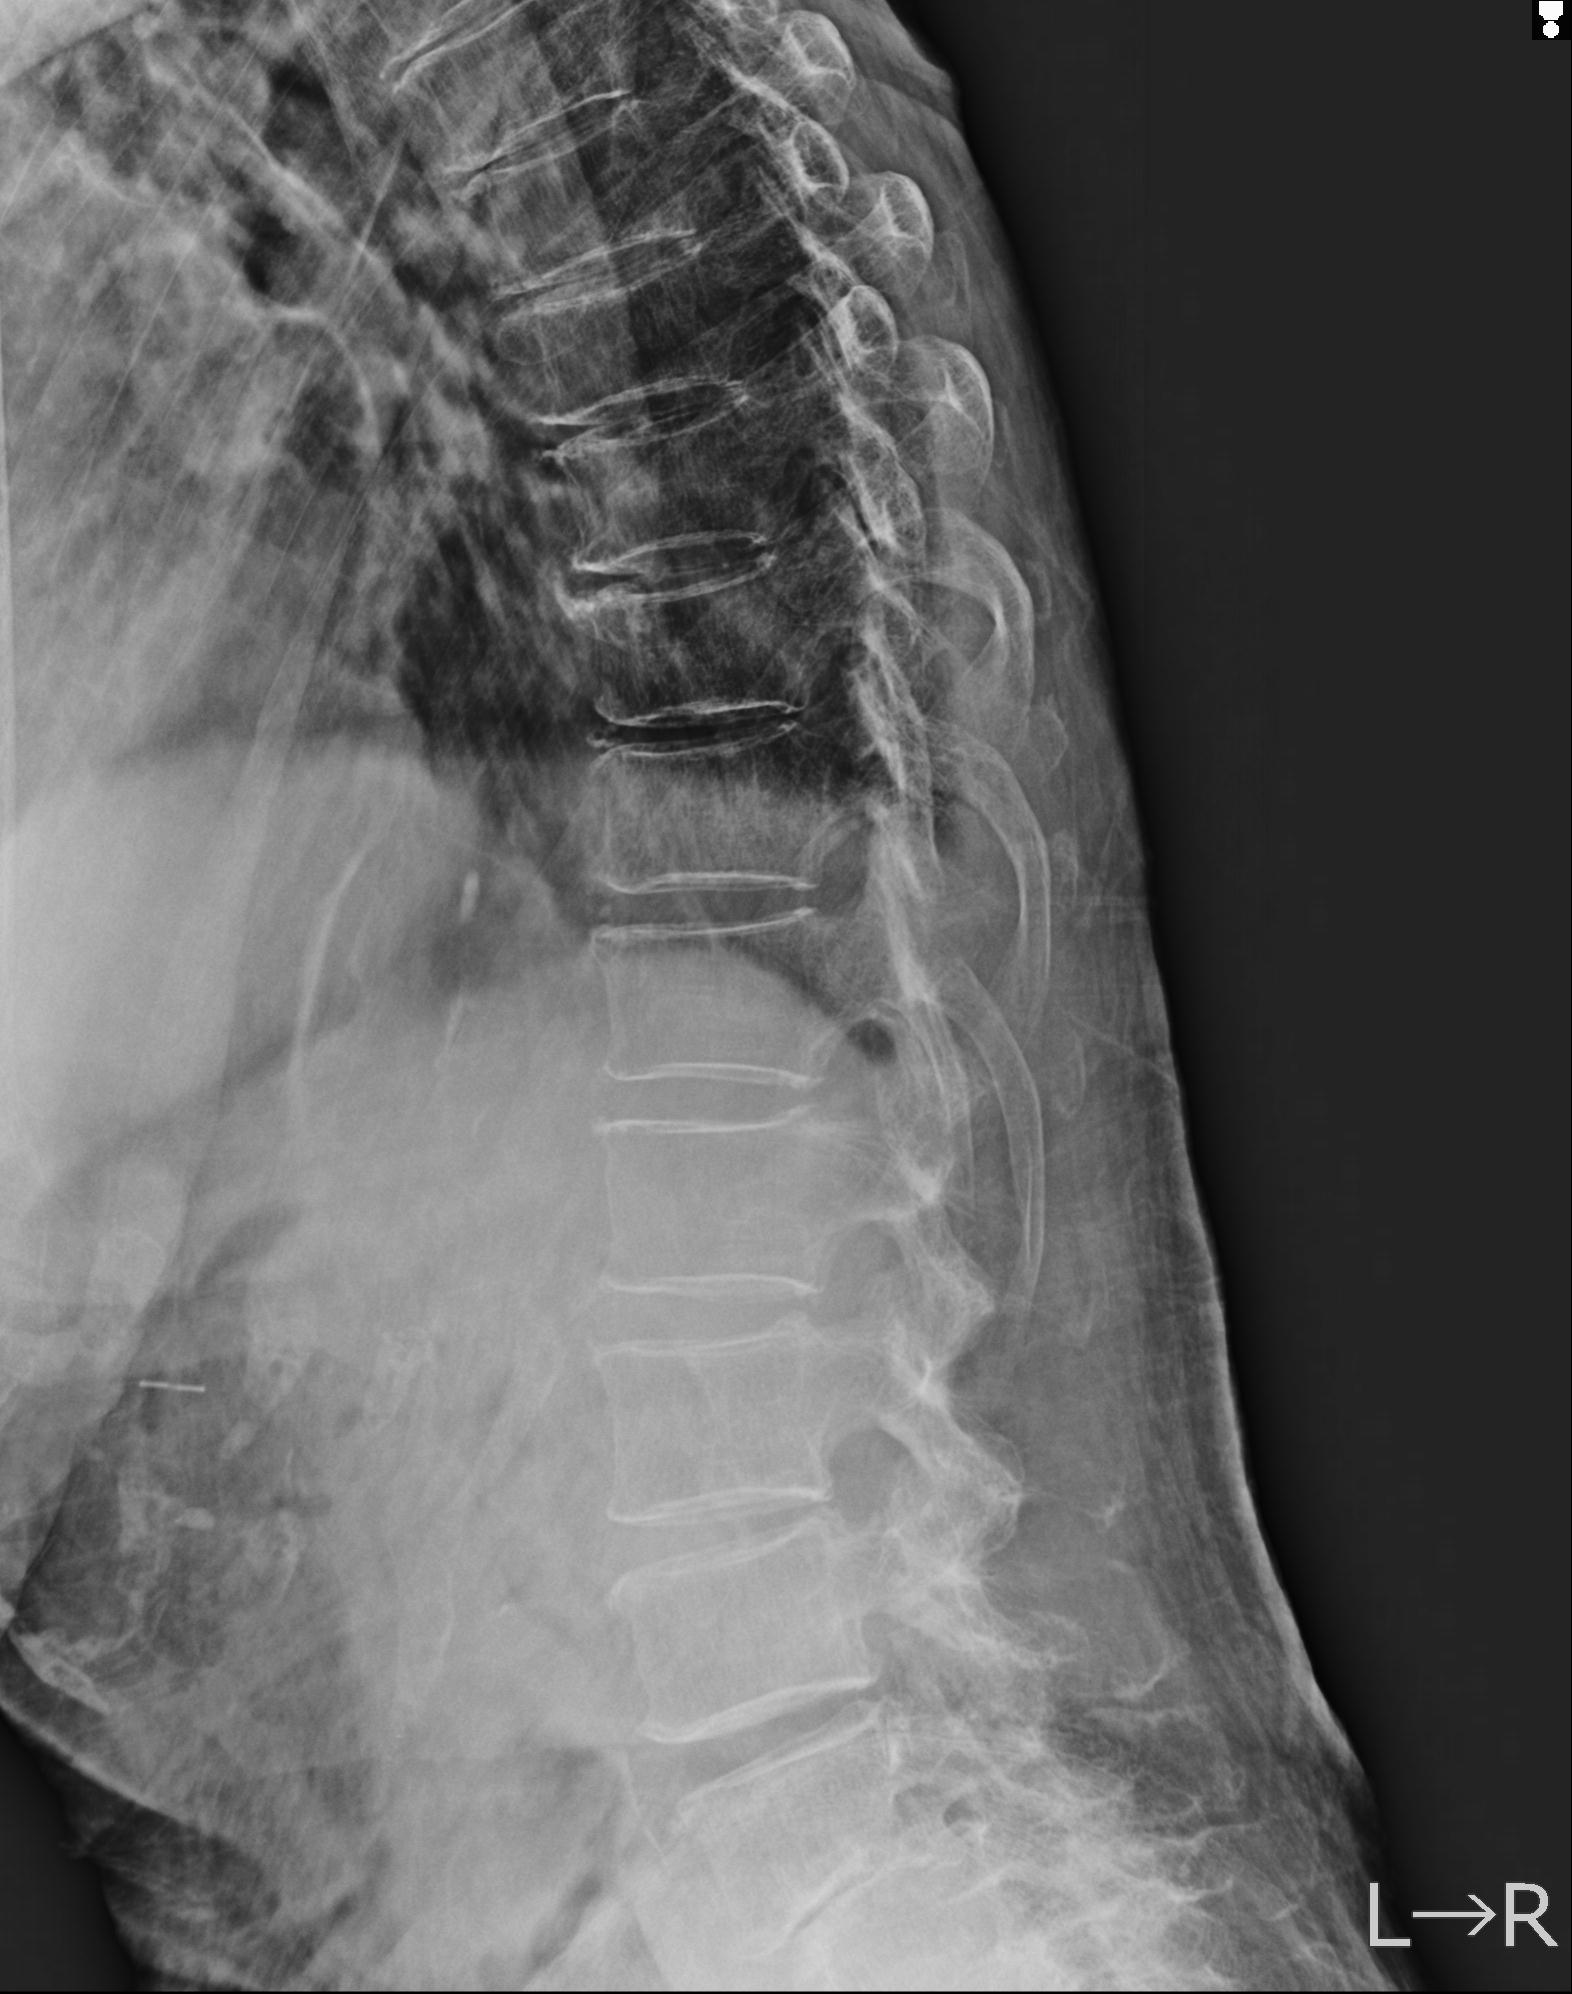

102916 2/1 と 3/22 腰椎 2R 74歳女性 LIFX